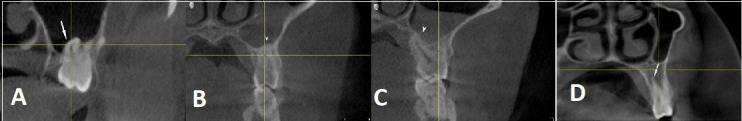

Results: Significant differences were found in sinus width between patients with full dentition and those with partial or complete edentulism (p<0.01). Male participants exhibited larger mean sinus dimensions compared to females in all dimensions. The maxillary sinus floor was inferior to the nasal floor in 91.5% of cases. Various types of sinus membrane abnormalities were observed, with normal membrane thickness in 53.75% of cases. Sinus septa were most frequently located on the roof of the sinus, and their frequency varied significantly among patients with different dentition statuses. The study also identified 274 Haller cells and documented several pathological changes, with mucosal thickening exceeding 3 mm being the most common alteration.